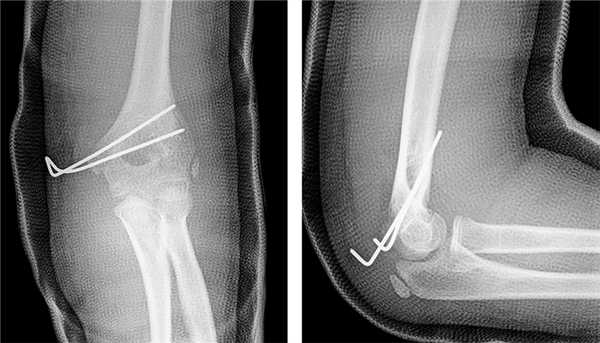

После утверждения протокола исследования местным этическим комитетом из базы данных детской больницы Salesi были отобраны записи всех пациентов, которые в период с 1 января 2014 г. по 31 декабря 2017 г. обращались в отделение неотложной помощи по поводу ПМН. Хирург-ортопед проводил классификацию ПМН по Watson-Jones (WJ) [9] и Papavasiliou [10]. Критериями включения в данное исследование были ПМН с внутрисуставным ущемлением в локтевом суставе, изолированные ПМН (III тип по WJ) или ПМН с вывихом предплечья (IV тип по WJ). В исследование включено 13 детей (5 мальчиков и 8 девочек), средний возраст которых составил 10,9 года (8-13 лет). Согласно записям в исследование было включено 6 пациентов с изолированным ПМН с внутрисуставным ущемлением в локтевом суставе (III тип по WJ) и 7 пациентов с ПМН с внутрисуставным ущемлением в локтевом суставе после закрытой репозиции по поводу сопутствующего заднелатерального вывиха предплечья (IV тип по WJ) (рис. 1). У 6 пациентов до операции наблюдалась парестезия в зоне иннервации локтевого нерва. В отделении неотложной помощи была выполнена рентгенография локтевого сустава в стандартных переднезадней и боковой проекциях. Для подтверждения внутрисуставного ущемления до операции одному пациенту была проведена трехмерная компьютерная томография (рис. 2). Перед исследованием было получено информированное согласие родителей/опекунов пациентов на использование медицинских карт их детей. Среднее время наблюдения составило 24,1 мес. (11-44 мес.).

Рис. 1. Пациент С. Вывих предплечья с внутрисуставным ущемлением медиального надмыщелка: а, б — рентгенограмма вывиха предплечья; в, г — рентгенограмма после устранения вывиха предплечья с внутрисуставным ущемлением медиального надмыщелка

Среднее время от травмы до операции составило 1,5 сут (0-4 сут). Во время операции пациенты находились в положении на спине, поврежденная верхняя конечность была расположена на рентгенопрозрачном операционном столе с ручным управлением. Операцию выполняли под внутривенной анестезией в условиях самостоятельного дыхания и с блокадой плечевого сплетения 0,5 % раствором ропивакаина под ультразвуковой навигацией. Для седации применяли мидазолам, фентанил вместе с кетамином и пропофолом. Местную анестезию осуществляли 0,5 % раствором ропивакаина. На пораженную руку накладывали нестерильный кровоостанавливающий пневматический жгут. Затем стерильное операционное поле обрабатывали от проксимальной части верхней конечности до кисти, кисть оставляли непокрытой. Руку обескровливали с помощью стерильного жгута Эсмарха, после чего пневматический жгут отпускали. Разрез начинали на 2-3 см выше локтевого сустава и на 1 см кзади от медиального надмыщелкового гребня и МН. Локтевой нерв был визуализирован и защищен с помощью ретрактора Хоманна, но ревизии нерва не выполняли. Место перелома осматривали, выявляли фрагмент медиального надмыщелка и удаляли его из полости локтевого сустава. С помощью ложки Фолькмана место перелома со стороны плечевой кости было освежено до губчатого вещества с сохранением ростковой зоны. Для расслабления мышц — сгибателей-пронаторов предплечью придавали положение пронации под углом 90° с согнутыми кистью и пальцами. Фрагмент медиального надмыщелка фиксировали скобкой Кодивиллы или Вебера так, чтобы не сломать сам фрагмент (рис. 3). После рентгенологического контроля правильности положения МН фиксировали через обе кортикальные пластины двумя скрещивающимися спицами Киршнера диаметром 1,5 мм (рис. 4).

Рис. 3. Пациент С. Заднемедиальный доступ к медиальному надмыщелку. Ретрактор Хоманна установлен под медиальным гребнем для защиты локтевого нерва, а фрагмент медиального надмыщелка временно фиксирован скобкой Кодивиллы

Рис. 4. Пациент С. Послеоперационная рентгенограмма: наложение изображений медиального надмыщелка и двух скрещивающихся спиц Киршнера диаметром 1,5 мм, проведенных через две кортикальные пластинки